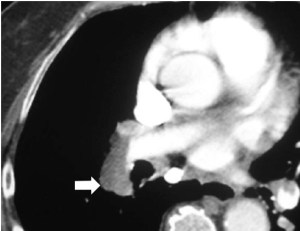

SIGNO DEL ÁREA DESNUDA

Cuando en la TC vemos líquido en situación dorsal al hígado (flecha), éste se encuentra en la cavidad pleural, ya que el líquido intraperitoneal no puede acumularse en esta zona debido a que el peritoneo se repliega sobre la cúpula hepática sin llegar a cubrir la parte posterior del hígado, es decir, que no hay cavidad peritoneal por detrás del hígado y, por tanto, la ascitis no puede ocupar este espacio.

En esta imagen también está presente, lógicamente, el Signo de la interfase.

SIGNO DE LAS CRURAS O DEL PILAR DIAFRAGMÁTICO DESPLAZADO

Cuando en la TC vemos que las cruras diafragmáticas están desplazadas lejos de la columna por líquido, éste está situado en la cavidad pleural (flecha). El líquido intraabdominal, a diferencia del derrame pleural, se sitúa lateral y anterior a las cruras.